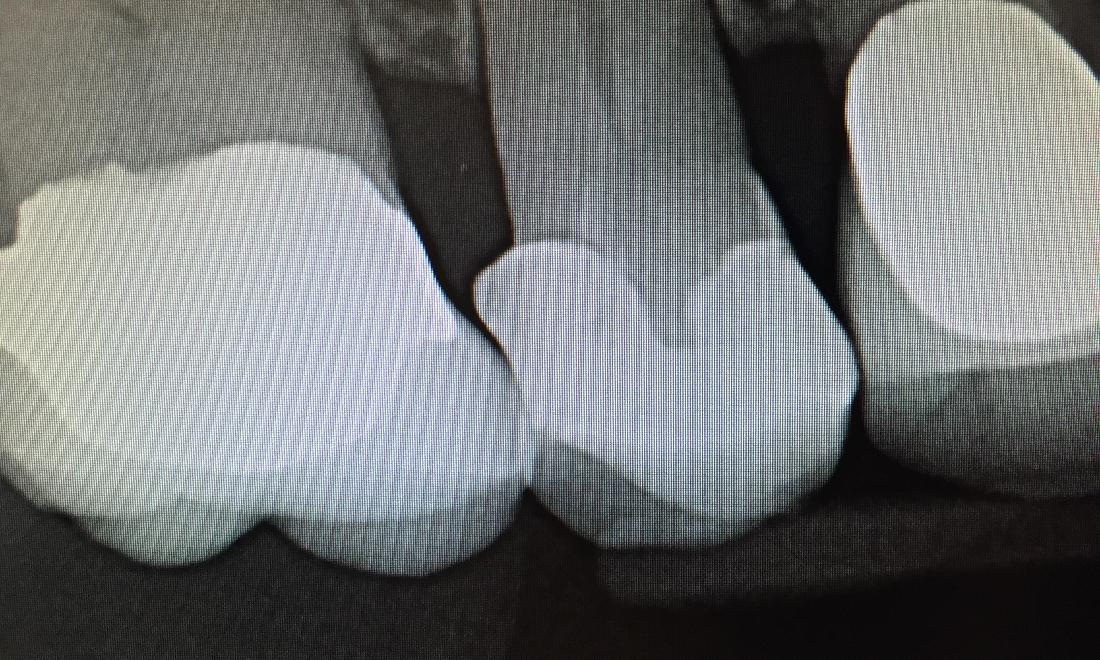

Poorly Contoured Restoration

Patient had a large amalgam filling with margin overhang the edge of the tooth, which can cause plaque and bacterial accumulation. This can potentially cause periodontal disease and tooth decay. The tooth was treated with all-ceramic crown to correct the overhang and prevent possible complications. Patient can now floss and maintain proper hygiene.